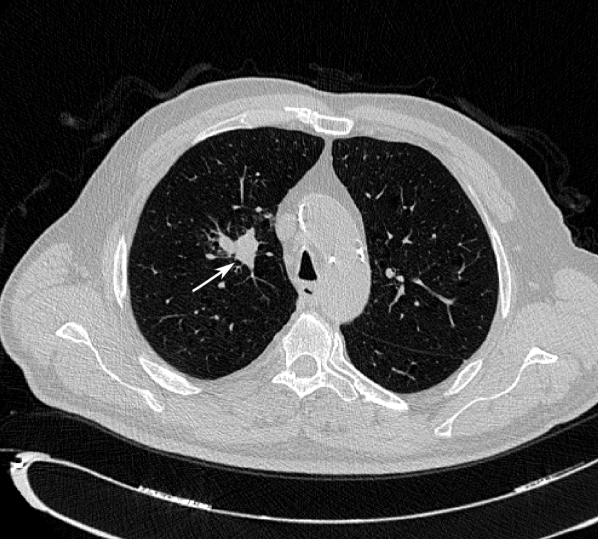

Table VI shows the CAD segmentation performance when compared to the segmentations by each radiologist. Overall, there is a statistically significant difference in the agreement between the CAD and the radiologist annotations and the agreement observed among the radiologists in both the LIDC-IDRI and the LNDb databases. Figure 5 shows examples of nodule segmentations by each radiologist and the automatic segmentation.

Refer to caption

Figure 5: Central axial view (51×\times51mm) of CAD segmentation examples (red) and ground truth annotations (green). Lines correspond to examples at the 5th percentile, mean and 95th percentile of MAD results obtained. Columns correspond to each radiologist. MAD obtained for each nodule shown at the lower right corner of each frame. Note that MAD is computed in 3D space whereas here only the central axial slice of each nodule is shown.